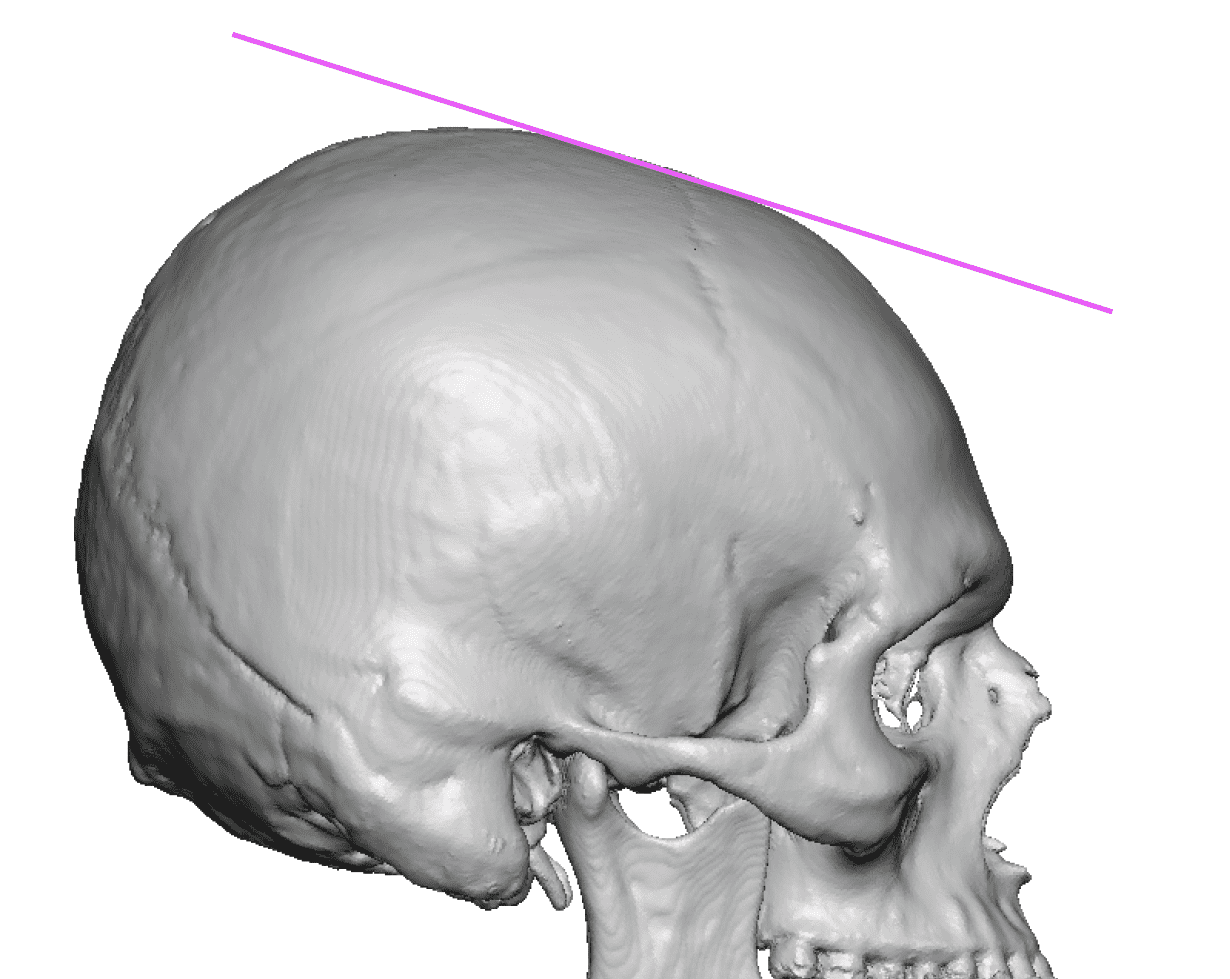

Desire for further skull augmentation after a primary skull implant.

Five years after an initial custom skull implant placement a new custom skull implant that increased the volume by 35% was placed.

Desire for further skull augmentation after a primary skull implant.

Five years after an initial custom skull implant placement a new custom skull implant that increased the volume by 35% was placed.